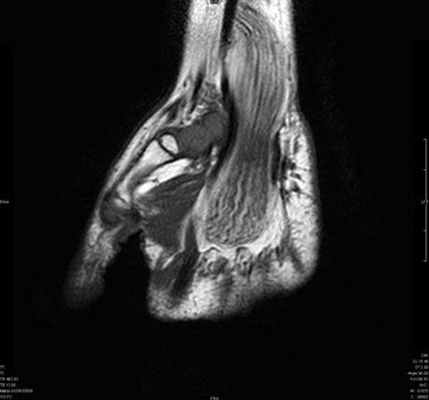

(Слева) Фронтальная Т2 ВИ с подавлением сигнала от жира: неоднородный отек костного мозга в полулунной кости без структурных изменений. Отрицательный локтелучевой индекс. Признаки не специфичны, следует иметь ввиду раннюю стадию развития остеонекроза.

(Справа) Рентгенография в ЗП проекции: многоочаговый остеонекроз вследствие применения стероидов. Полулунная кость имеет неоднородную плотность и коллапс проксимальной суставной поверхности. Проксимальный полюс ладьевидной кости уплощен. Однако остеонекроз ладьевидной кости является, как правило, посттравматическим, прием стероидов является фактором риска. (Слева) Рентгенография в ЗП проекции: несросшаяся линия перелома ладьевидной кости. Это, вероятное всего, истинное несращение, так как края перелома склерозированы, с субхондральной кистозной дегенерацией. Нет выраженного склероза проксимального полюса.

(Справа) Фронтальная Т1 МР-И, этот же случай: неоднородный низкий сигнал в проксимальном и дистальном отделах ладьевидной кости. Линия перелома видна нечетко. (Слева) Фронтальная T1FS постконтрастная МР-И: усиление дистального полюса, но низкий сигнал проксимального полюса, что указывает на отсутствие кровоснабжения. Несмотря на то, что здесь, вероятно, нежизнеспособные ткани, коллапса нет; оперативное лечение может иметь успех.

(Справа) Рентгенография запястья в ЗП проекции: у пациента с СКВ и остеонекрозом наблюдается коллапс проксимального полюса ладьевидной костив Определяется неровность суставной поверхности лучевого края полулунной кости и субхондральный перелом. При болезни Кинбека изменения со стороны лучевого края кости более характерны, чем со стороны локтевого края.